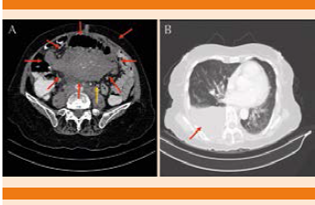

En noviembre de 2016 acudió nuevamente al servicio de urgencias por padecer astenia, adinamia, pérdida de peso y dolor en el epigastrio, de tipo urente, transfictivo. Se realizó un ultrasonido abdominal que reportó probable lesión hepática con infiltración a epiplón, los marcadores tumorales se reportaron alterados: Ca 125 en 579.3 ng/mL y Ca 19.9 en 87 U/mL. La tomografía abdominal con doble contraste mostró un tumor retroperitoneal y derrame pleural derecho de más de 50% del área pulmonar total. Fue valorada por el servicio de hematología donde se consideró la posibilidad de recaída del mieloma múltiple o una segunda neoplasia (Figuras 1 y 2).

Figura 2 A. Tumor retroperitoneal en corte axial (flecha roja), conglomerado ganglionar (flecha amarilla). B. Derrame pleural derecho (ventana para pulmón).